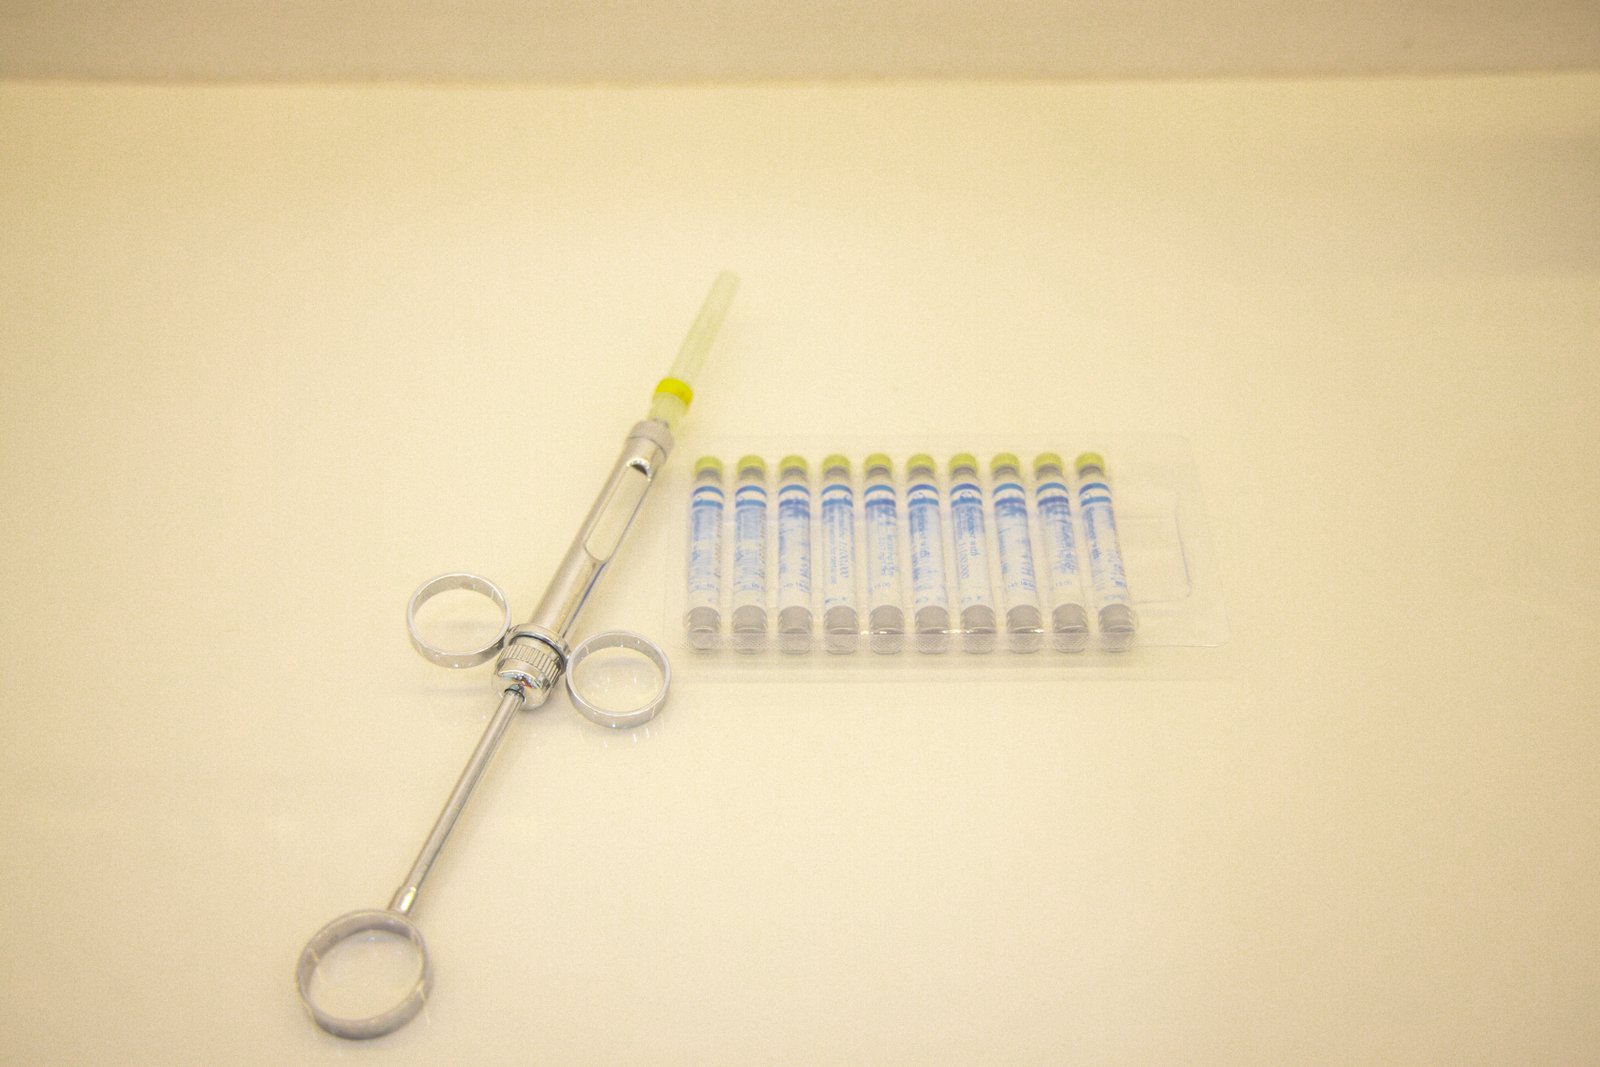

Specialized endodontic care to save infected teeth and relieve pain.

Safe, comfortable extractions with clear aftercare guidance.

See every stage of our treatments with clear, step-by-step visuals that reflect our precision and care.